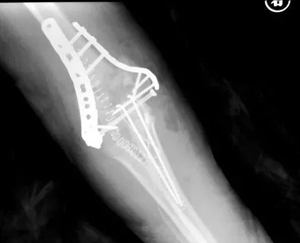

儿童复杂肘关节骨折及脱位

随着时代的进步和运动方式的变化,儿童肘关节复杂骨折及脱位发生率呈明显上升趋势,并发症(如术后肘关节僵硬)发生率也较高,对治疗提出了挑战。积水潭医院小儿骨科通过多年的治疗经验结合现代的治疗理念,已经形成了比较成熟的治疗方法,在恢复骨骼结构稳定性的同时规范地进行功能训练,最大限度地恢复肘关节的功能。